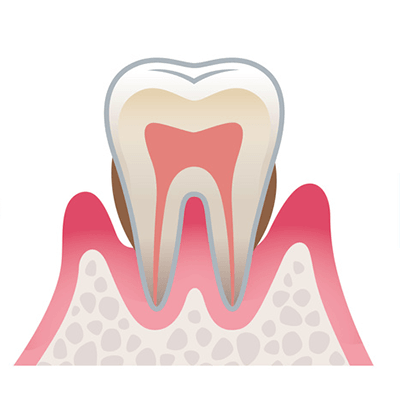

歯周病とは、歯と歯ぐきのすき間(歯周ポケット)から細菌が侵入し、歯肉に炎症を引き起こしたり、歯を支える骨(歯槽骨)などが溶けたりする病気です。歯を失う原因として、むし歯よりも多くの割合を占めています。炎症が歯肉だけに留まっている状態を「歯肉炎」、炎症が歯槽骨や歯根膜にまで広がっている状態を「歯周炎(歯槽膿漏)」といいます。むし歯と異なり痛みがなく、気づかないうちに進行する特徴があり、歯周ポケットが深くなっていくと、歯肉が腫れたり、歯がグラグラしたりして、ものが噛めなくなり、歯が自然に抜け落ちるほど重症になることもあります。

健康な状態

薄いピンク色の歯肉で、歯と歯ぐきのすき間(歯周ポケット)がなく引き締まっています。ブラッシング時に出血しません。

軽度歯周病

歯ぐきに炎症が起き、歯周ポケットが深くなります。痛みはまだありませんが、ブラッシング時や硬いものを食べると出血することがあります。

赤く歯ぐきが腫れあがり、歯と歯肉との間にプラーク(歯垢)がたまります。

中度歯周病

歯ぐきだけではなく、歯を支える顎の骨にも炎症が進んだ状態です。炎症が慢性化し骨が溶けはじめます。歯周ポケットが深くなり歯がグラつきはじめます。口臭もあり、歯が浮いたような感じもあります。

全体的に歯肉が赤く腫れあがり、変色がひどくなります。

重度歯周病

歯根を支える骨がほとんど溶けています。歯周ポケットがかなり深くなり、歯のグラつきも、歯根が露出することでさらにひどくなります。口臭がきつくなり、膿も出て、放っておくと歯が抜け落ちてしまいます。

歯肉は赤紫色で、歯と接している歯肉がさらに腫れあがります。歯と歯の間が広がり、食べ物もよく詰まるようになります。